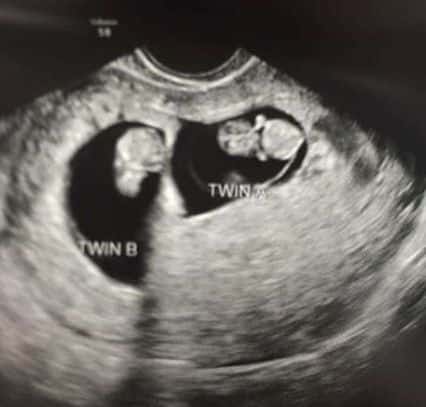

Early Twin Ultrasound at 7 Weeks

The earliest your doctor would likely order an ultrasound confirming twins would be 4 weeks pregnant. But unless you are going through fertility treatments, doing an ultrasound before 6 weeks isn’t very common, with the exception of complications. Women who are going through fertility treatments or have early complications may be able to have an early twin ultrasound at 4 or 5 weeks pregnant and find out they are pregnant with twins.

At four to five weeks after a pregnant woman’s last period the ultrasound commonly shows a small collection of fluid within the lining of the uterus that represents the early development of the gestational sac. At about five and a half weeks after a pregnant woman’s last period the ultrasound typically shows a gestational sac and within it we can see a 3-5 mm bubble-like structure, which is the yolk sac. At approximately six weeks after a pregnant woman’s last period, we can see a small fetal pole, one of the first stages of growth for an embryo, which develops alongside the yolk sac.

Can You Tell at 7 Weeks if Its Twins?

Yes! You’d need to have an ultrasound at 7 weeks to confirm a twin pregnancy. Your twin belly at 7 weeks may not look like much of a belly at all, so getting in to your doctor for an ultrasound is key to find out if you’re really having twins.